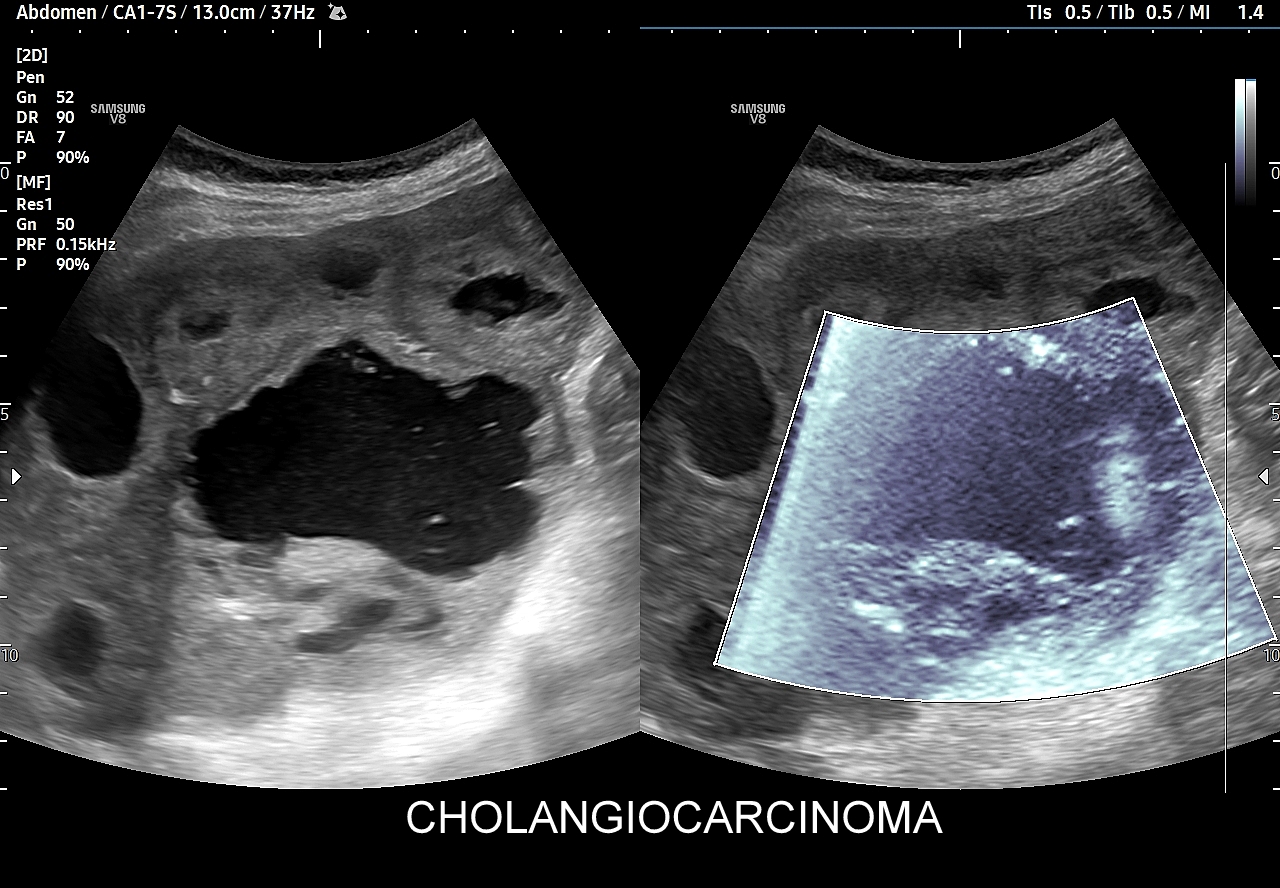

Tę formę rozwoju ECC prezentują załączone w niniejszym artykule skany. Na skanach zauważyć można znaczne poszerzenie dróg żółciowych wewnątrzwątrobowych w całym narządzie, zastój żółci z obecnym artefaktem migotania w trybie color-Doppler, tkankowe nacieki wątrobowe w poszerzonych drogach żółciowych. Należy zwrócić uwagę na przydatność trybu MVI w ocenie unaczynienia zmian tkankowych w przewodach żółciowych.